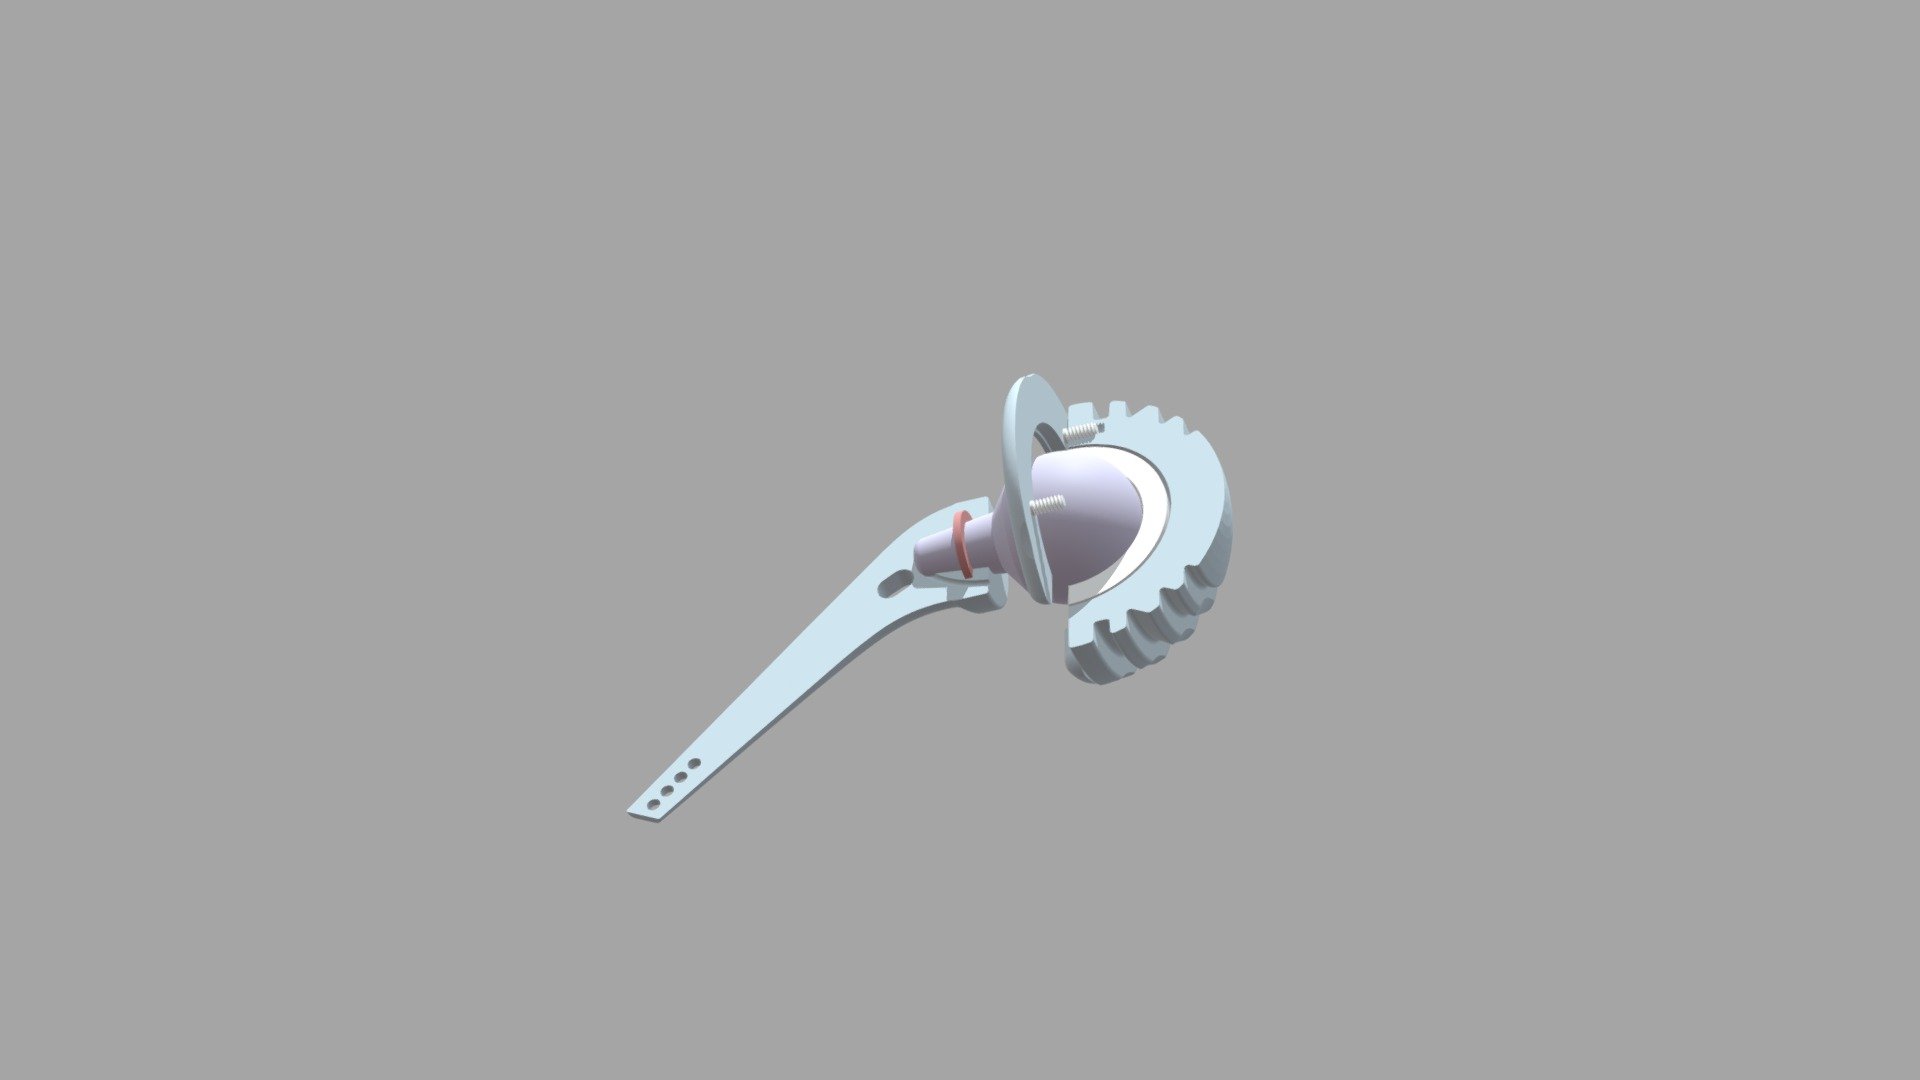

HIP REPLACEMENT - 3D Model By Holos Studios [447b2ca] - Sketchfab

![HIP REPLACEMENT - 3D model by Holos Studios [447b2ca] - Sketchfab](https://media.sketchfab.com/models/447b2ca373a549fea80b0337f2d53b48/thumbnails/083cf9a4c3734bac8a124be9bbd34c46/5d7515d0972b4c21afd6cd572e59f309.jpeg) sketchfab.com

sketchfab.com

Replacement Hip 3D - TurboSquid 1520195

www.turbosquid.com

www.turbosquid.com

hip replacement 3d turbosquid c4d

Hip Replacement - 3D Model By BlueLou

www.renderhub.com

www.renderhub.com